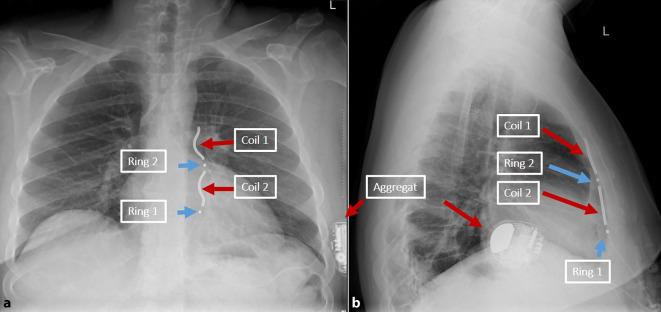

As an alternative to transvenous ICD systems, two non-transvenous ICD systems have been established in recent years: The subcutaneous ICD (S-ICD), which has been established for several years, has a presternal electrode that is implanted subcutaneously and offers a shock function and, to a limited extent, post-shock pacing. In addition, the extravascular ICD (EV-ICD) has been available in Europe since 2023 which does not require transvenous electrodes and offers the option of providing patients with antibradycardic and antitachycardic stimulation in combination with a conventional ICD function. The lead of this device is implanted substernally. Initial implantation results are promising in terms of safety and effectiveness. Both systems avoid possible complications of transvenous electrodes. This article provides practical guidance for the implantation technique and possible complications.

作为经静脉植入式心律转复除颤器(ICD)系统的替代方案,近年来已建立了两种非经静脉ICD系统:皮下ICD(S-ICD)已应用数年,其具有一个皮下植入的胸骨前电极,具备除颤功能,并在一定程度上具备电击后起搏功能。此外,血管外ICD(EV-ICD)自2023年起在欧洲上市,它不需要经静脉电极,并提供了结合传统ICD功能为患者提供抗心动过缓和抗心动过速刺激的选项。该设备的导线植入胸骨后。就安全性和有效性而言,初始植入结果很有前景。两种系统都避免了经静脉电极可能出现的并发症。本文为植入技术和可能出现的并发症提供了实用指南。